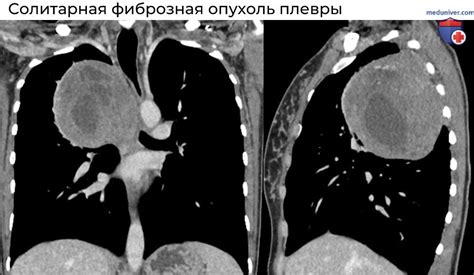

Утолщение костальной плевры может сопровождаться различными симптомами, такими как боль в груди, затрудненное дыхание, кашель, ощущение сдавленности. Однако утолщение костальной плевры часто является следствием основного заболевания и может быть обнаружено только при проведении дополнительных исследований, таких как рентген грудной клетки или компьютерная томография.

| Рентгенография грудной клетки | Рентгенологическое исследование позволяет получить изображение грудной клетки, чтобы выявить изменения в легочной и плевральной области. Оно может помочь определить утолщение костальной плевры и обнаружить другие патологии. |

| Компьютерная томография | Использование компьютерной томографии позволяет получить 3D-изображение грудной клетки и обнаружить патологические изменения, включая утолщение костальной плевры. Этот метод часто применяется в случаях, когда другие методы исследования не позволяют однозначно диагностировать состояние плевры. |